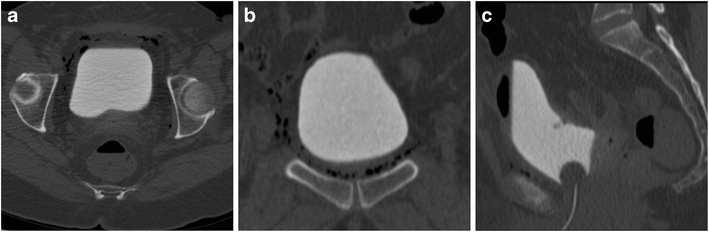

The symptoms of pcos and hormonal imbalance can be awful and sometimes downright devastating so anything that alleviates some of these symptoms might seem welcome. What happens after the operation? On the morning of the first day after surgery, the urine drainage catheter will be removed, and your bladder will fill normally.

The bladder is very close to operating site for a hysterectomy and occasionally it can get damaged during the operation <2%.